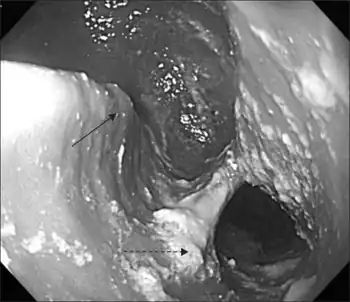

| Killian–Jamieson diverticulum. Arrowhead points at the closed upper esophageal sphincter, arrow points at the diverticulum partly filled with contrast medium. | |

A Killian–Jamieson diverticulum is an outpouching of the esophagus just below the upper esophageal sphincter.[1]

The physicians that first discovered the diverticulum were Gustav Killian and James Jamieson. Diverticula are seldom larger than 1.5 cm, and are less frequent than the similar Zenker's diverticula. As opposed to a Zenker's, which is typically a posterior and inferior outpouching from the esophagus, a Killian–Jamieson diverticulum is typically an anterolateral outpouching at the level of the C5-C6 vertebral bodies, due to a congenital weakness in the cervical esophagus just below the cricopharyngeal muscle. It is usually smaller in size than a Zenker's diverticulum, and typically asymptomatic.[2] Although congenital, it is more commonly seen in elderly patients.[3]